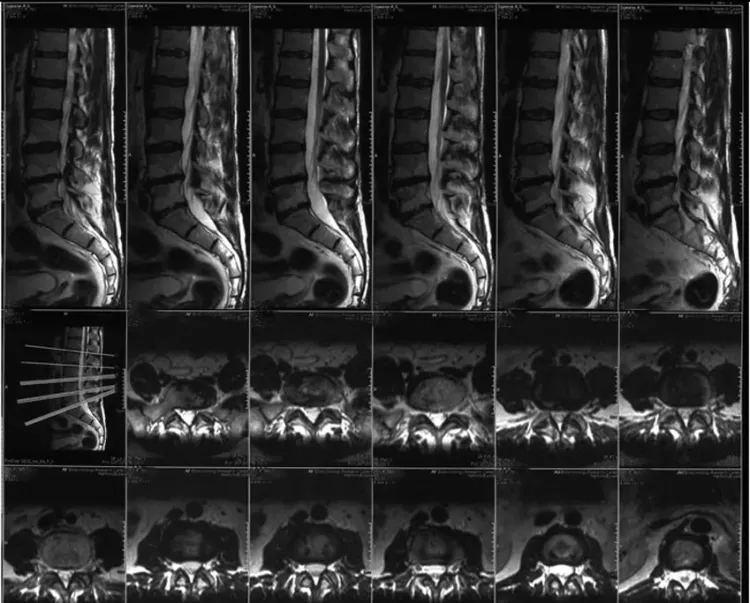

МРТ поясничного отдела – это современный и безопасный метод диагностики, который позволяет получить высококачественные изображения позвоночника и окружающих тканей. Этот вид исследования не использует ионизирующее излучение, что делает его более безопасным по сравнению с рентгеном или компьютерной томографией. В Нахабино доступно множество медицинских центров, где проводятся такие анализы, что значительно повышает доступность услуги для жителей.

Исследование помогает врачам быстро и точно выявлять различные патологии, включая грыжи, остеохондроз и воспалительные процессы. Для того чтобы сфокусироваться на картах состояния здоровья пациента, важно выполнять томографию по показаниям, чтобы получить максимально полную и достоверную информацию о состоянии поясничного отдела. Тщательная интерпретация полученных данных позволяет врачам разрабатывать наиболее эффективные планы лечения, подходящие именно для каждого пациента.

Что показывает МРТ поясничного отдела в Нахабино

Метод позволяет выявить множество патологий и отклонений, среди которых можно выделить следующие:

- Грыжи межпозвоночных дисков.

- Остеохондроз.

- Воспалительные заболевания.

- Травмы позвоночника.

- Сужение позвоночного канала.

- Опухоли.

Каждое из указанных состояний может иметь серьезные последствия, и их своевременная диагностика при помощи МРТ помогает найти наиболее эффективные методы лечения и улучшить качество жизни пациента.